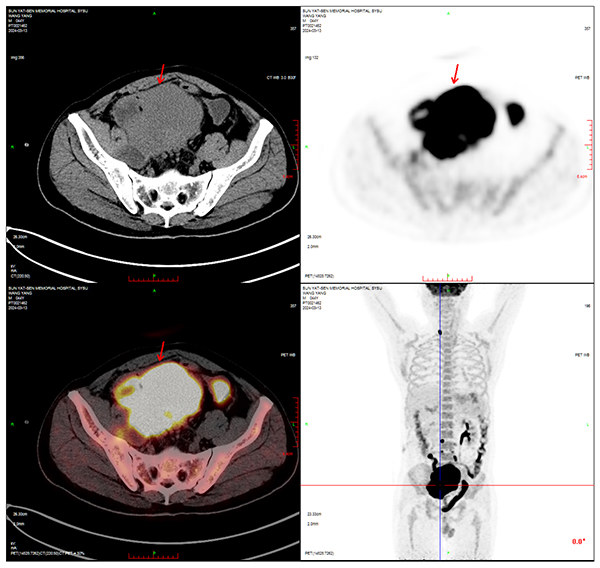

江树迅速办理了住院,并接受了更为精确的全身PET-CT检查。结果触目惊心:右侧输尿管中下段盘踞着 115×93×117mm 的恶性肿块,包裹侵犯乙状结肠和右侧盆壁,还引发多处淋巴结转移。穿刺活检的病理结果最终确认为高级别尿路上皮癌,伴有HER-2(2+)表达,综合分期为T4N2M0,属于IV期局部晚期伴区域淋巴结转移,预后极差。

◎ 2024年3月13日,PET-CT检查结果。/ 图:受访者供图

PET-CT复查结果带来了巨大惊喜:原本直径超过11厘米的巨大肿瘤,缩小至2.1×3.2×2.2厘米,体积缩小超过80%!同时,转移的淋巴结数量减少、体积明显缩小。疗效评估达到“显著缓解”。